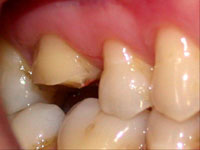

Fig. 3

Determinação do bisel chanfrado ou côncavo vestibular com a ponta diamantada n°3118 (KG Sorensen).

O dente 16 apresentava apenas duas cúspides remanescentes e fragilizadas, as quais precisaram ser reduzidas por desgaste (Fig. 1). Após a redução cuspídea, restou uma coroa clínica curta e com assoalho pulpar plano. Devido a essas condições não havia a possibilidade de preparar uma caixa oclusal, os degraus proximais que determinam uma cavidade MOD pois a polpa seria atingida , assim como, estrutura para reter uma coroa total. (Fig. 1, 2 e 3).

O ângulo cavo-superficial foi preparado com ponta diamantada (nº3118 da KG Sorensen) girando em baixa velocidade, formando um bisel chanfrado em toda extensão da margem vestibular e lingual do dente (Fig. 3). Por sua vez, as margens proximais foram biseladas com ponta diamantada de diâmetro menor (nº1111 da KG Sorensen) estendendo-se para vestibular e lingual com o intuito de manter o término cavitário separado do dente vizinho e manter a distância biológica horizontal (espaço para acomodar a papila sem ser comprimida, facilitar o acabamento das margens de esmalte, das bordas da restauração, a moldagem e o espaço para higienização) (Fig. 4 e 5).